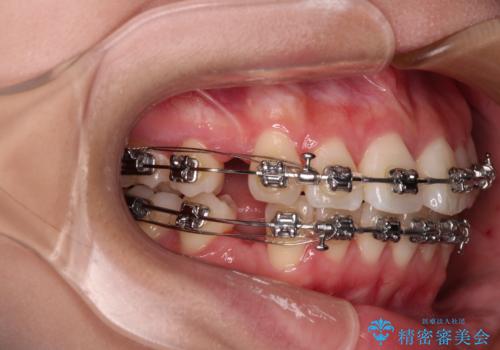

- 矯正装置

- メタルブラケット

- 前歯がくちばしのように飛び出していることを気にして来院された患者様です。

唇が前方に突出している横顔が気になっているため、上下左右の第一小臼歯4本を抜歯し、ワイヤー装置にて矯正治療を行うこととしました。